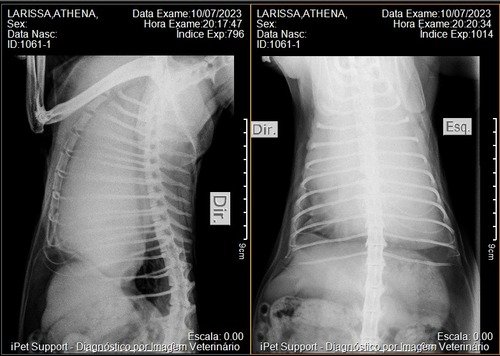

Assim que fizemos exames de sangue, e raio X descobrimos o linfoma mediastinal.